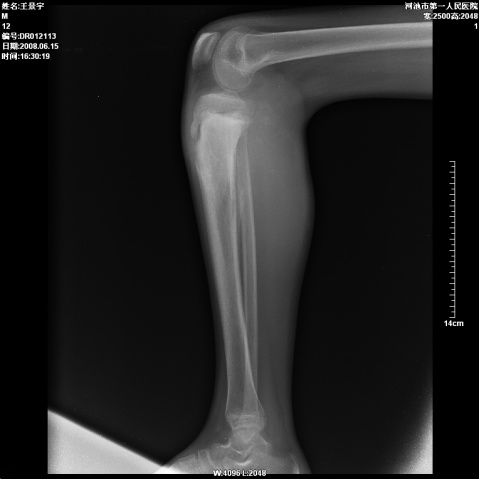

以下是引用随光逐影在2008-6-23 15:30:00的发言:[br]胫骨中上段骨肉瘤(临床表现:好发年龄+好发部位。ct表现:骨质破坏+肿瘤新生骨+骨膜反应并破坏,形成codman氏三角+软组织肿块)。